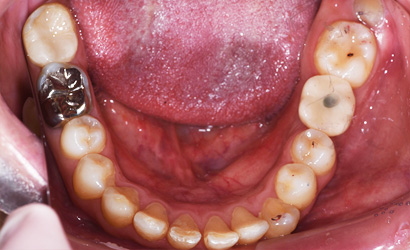

| 年齢・性別 | 20代・男性 |

|---|---|

| 主訴・治療部位 | 歯が痛い 下顎左側第一大臼歯 |

| 治療内容 | インプラント治療 |

| 治療費 | 保険外治療 約560,000円 |

| 治療期間 | 約半年 |

| リスク・副作用 | 外科処置により痛み、腫れを伴う |